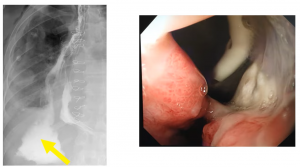

Anastomotic leaks: These significantly increase morbidity and mortality, affect a patient’s quality of life, also expensive to the health service, and lead to early disease recurrence and poor survival; you can see the types below:

Below you can see a cervical anastomotic leak Type 1:

A radiological intra-thoracic Type 1 leak:

A Type 2 leak can be very large: